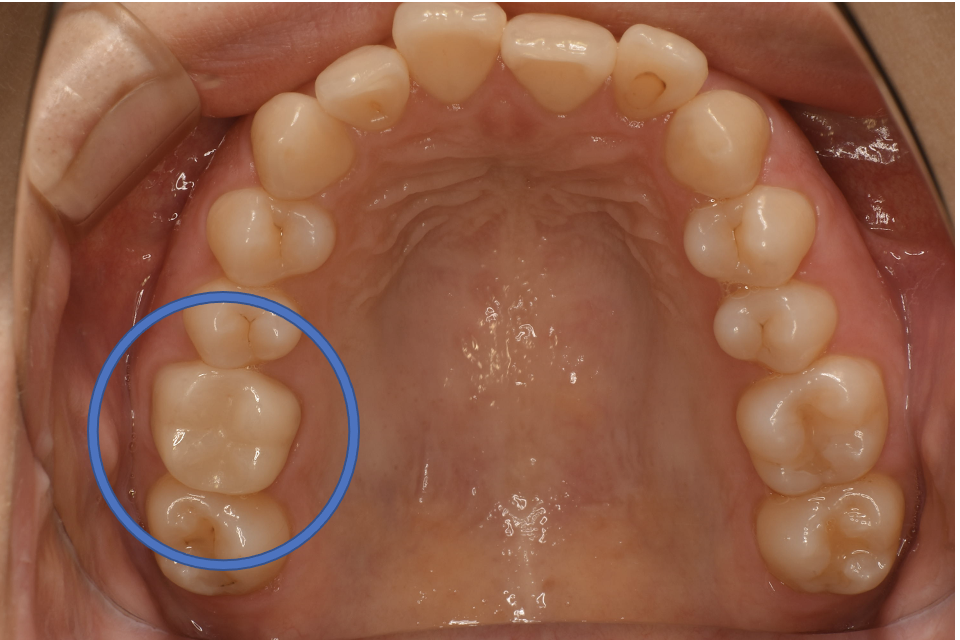

After

| 治療方法 | セラミックインレー(E-MAX In) 虫歯などで失った歯質を天然歯と同じ色・質感のセラミックで補う治療法です。金属を使用する治療と比べて、審美性だけではなく、耐久性や体の負担が少ないという面でも優れていると注目されています。従来のセラミックと比べて天然歯と同程度の強度であり、耐久性が高くなっています。どのくらいもつかは使用状況や部位、メンテナンスの有無などによって大きく変わってきます。透明感があり、キレイで自然な色調を表現できます。歯と分子レベルの化学結合によって吸着するため隙間ができることが少なく、虫歯にもなりにくいと言われています。 そして、金属アレルギーのリスクがありません。 |

| 備考 | 院長より プラスティック修復部の内部に虫歯が進行してしまっていたケースです。中を開けて見てみると、外から想像するよりもはるかに虫歯が 広がってしまっていました。幸運にも神経を保存できたので、生きた臓器としてまだ使うことが可能です。今回は部分的な詰め物で対応することができたケースです。 |